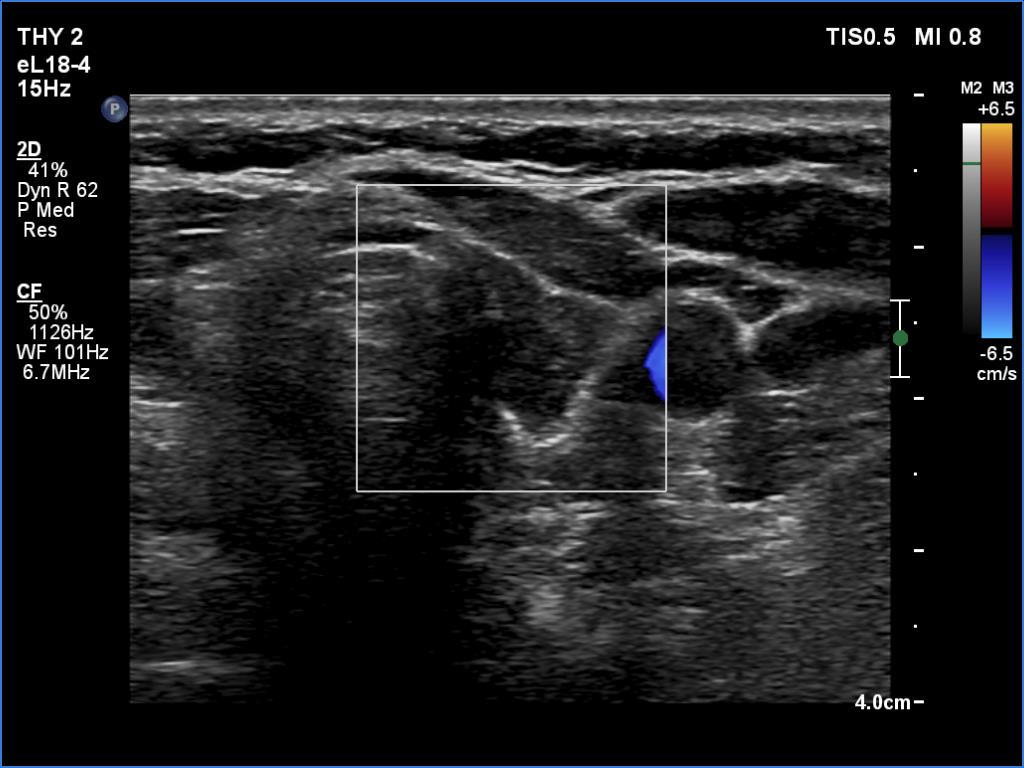

Left lobe, transverse view, color Doppler mode. This lobe is also avascular.